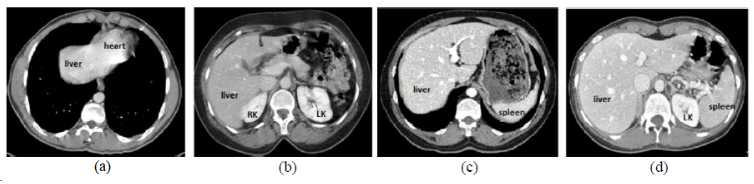

CHAOS

| CHAOS | 肝/肾/脾 | 分割 | CT+MRI | 40CT+120MRI | 0/1标签 | dcm | CC 4.0 |

CHAOS是一个多脏器,多模态分割数据集。